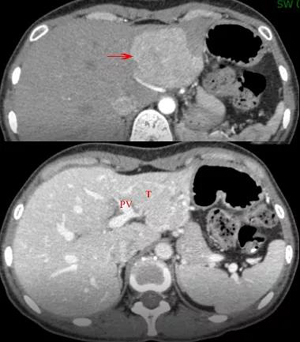

患者为一例年轻女性,发现左肝S2、3段占位病灶三年余,就诊时肿瘤已缓慢进展至6cm大小。手术前的影像学评估考虑病变为良性的肝脏腺瘤或局灶性结节增生,由于肿瘤尾侧端非常贴近左侧肝蒂且与正常肝实质区分不显著,如能顺利行左肝外叶II、III段的切除会比较理想,但恐怕会存在肿瘤与左侧肝蒂结构难以分离的情况,若实施左半肝切除对于良性病变而言损失过多正常肝组织会比较惋惜。手术主刀医师吴全医生经过慎重考虑后决定使用Pinpoint荧光显像导航技术为患者施行腹腔镜下的精准肝切除手术。

目前腹腔镜下肝脏切除手术是治疗肝脏肿瘤的标配方式,以往在腔镜手术中循肝静脉走行保证劈肝平面不跑偏很考验肝外科医师的功力。新近开展应用的 Pinpoint荧光显像导航技术是利用吲哚青绿(Indocyanine Green, ICG)荧光染料做为标记物,这种染料由肝细胞吸收从胆道排泄,由于肿瘤细胞摄取ICG后比健康肝细胞排泄得慢,易发生滞留,故利用这一特性将肿瘤或要切除的肝段用ICG进行标记,再用700-800nm波长的光波照射,被染料标记部分可发射λ840nm的光波,最后经特制装置接收并转换为荧光或彩色荧光呈现至显示器。借助这漂亮的荧光,肝脏外科医师就能够在断肝的过程中直观地看到需要切除的肝脏与需要保留的肝脏之间的分界线,有了清晰的路标指引,手术刀即能始终保持在正确的离断平面上,不会因为走歪而导致病肝切除不够或健侧肝组织损失过多,可以说荧光腹腔镜是开展微创、精准肝切除的一大利器。